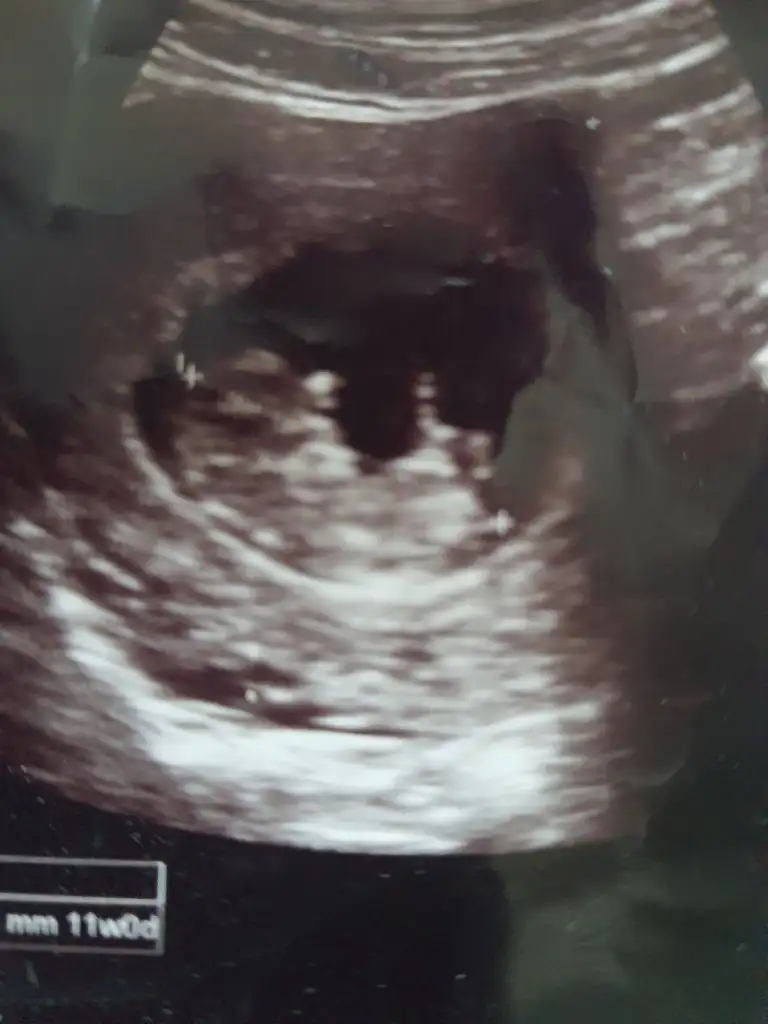

Birde bana bakarmisiniz hanımlar çok merak ediyorum ve hiç anlamıyorum 😊

Benim bebiş te 6+6iken karından Ultrason sizin tahmininiz nedir kızlar ☺️